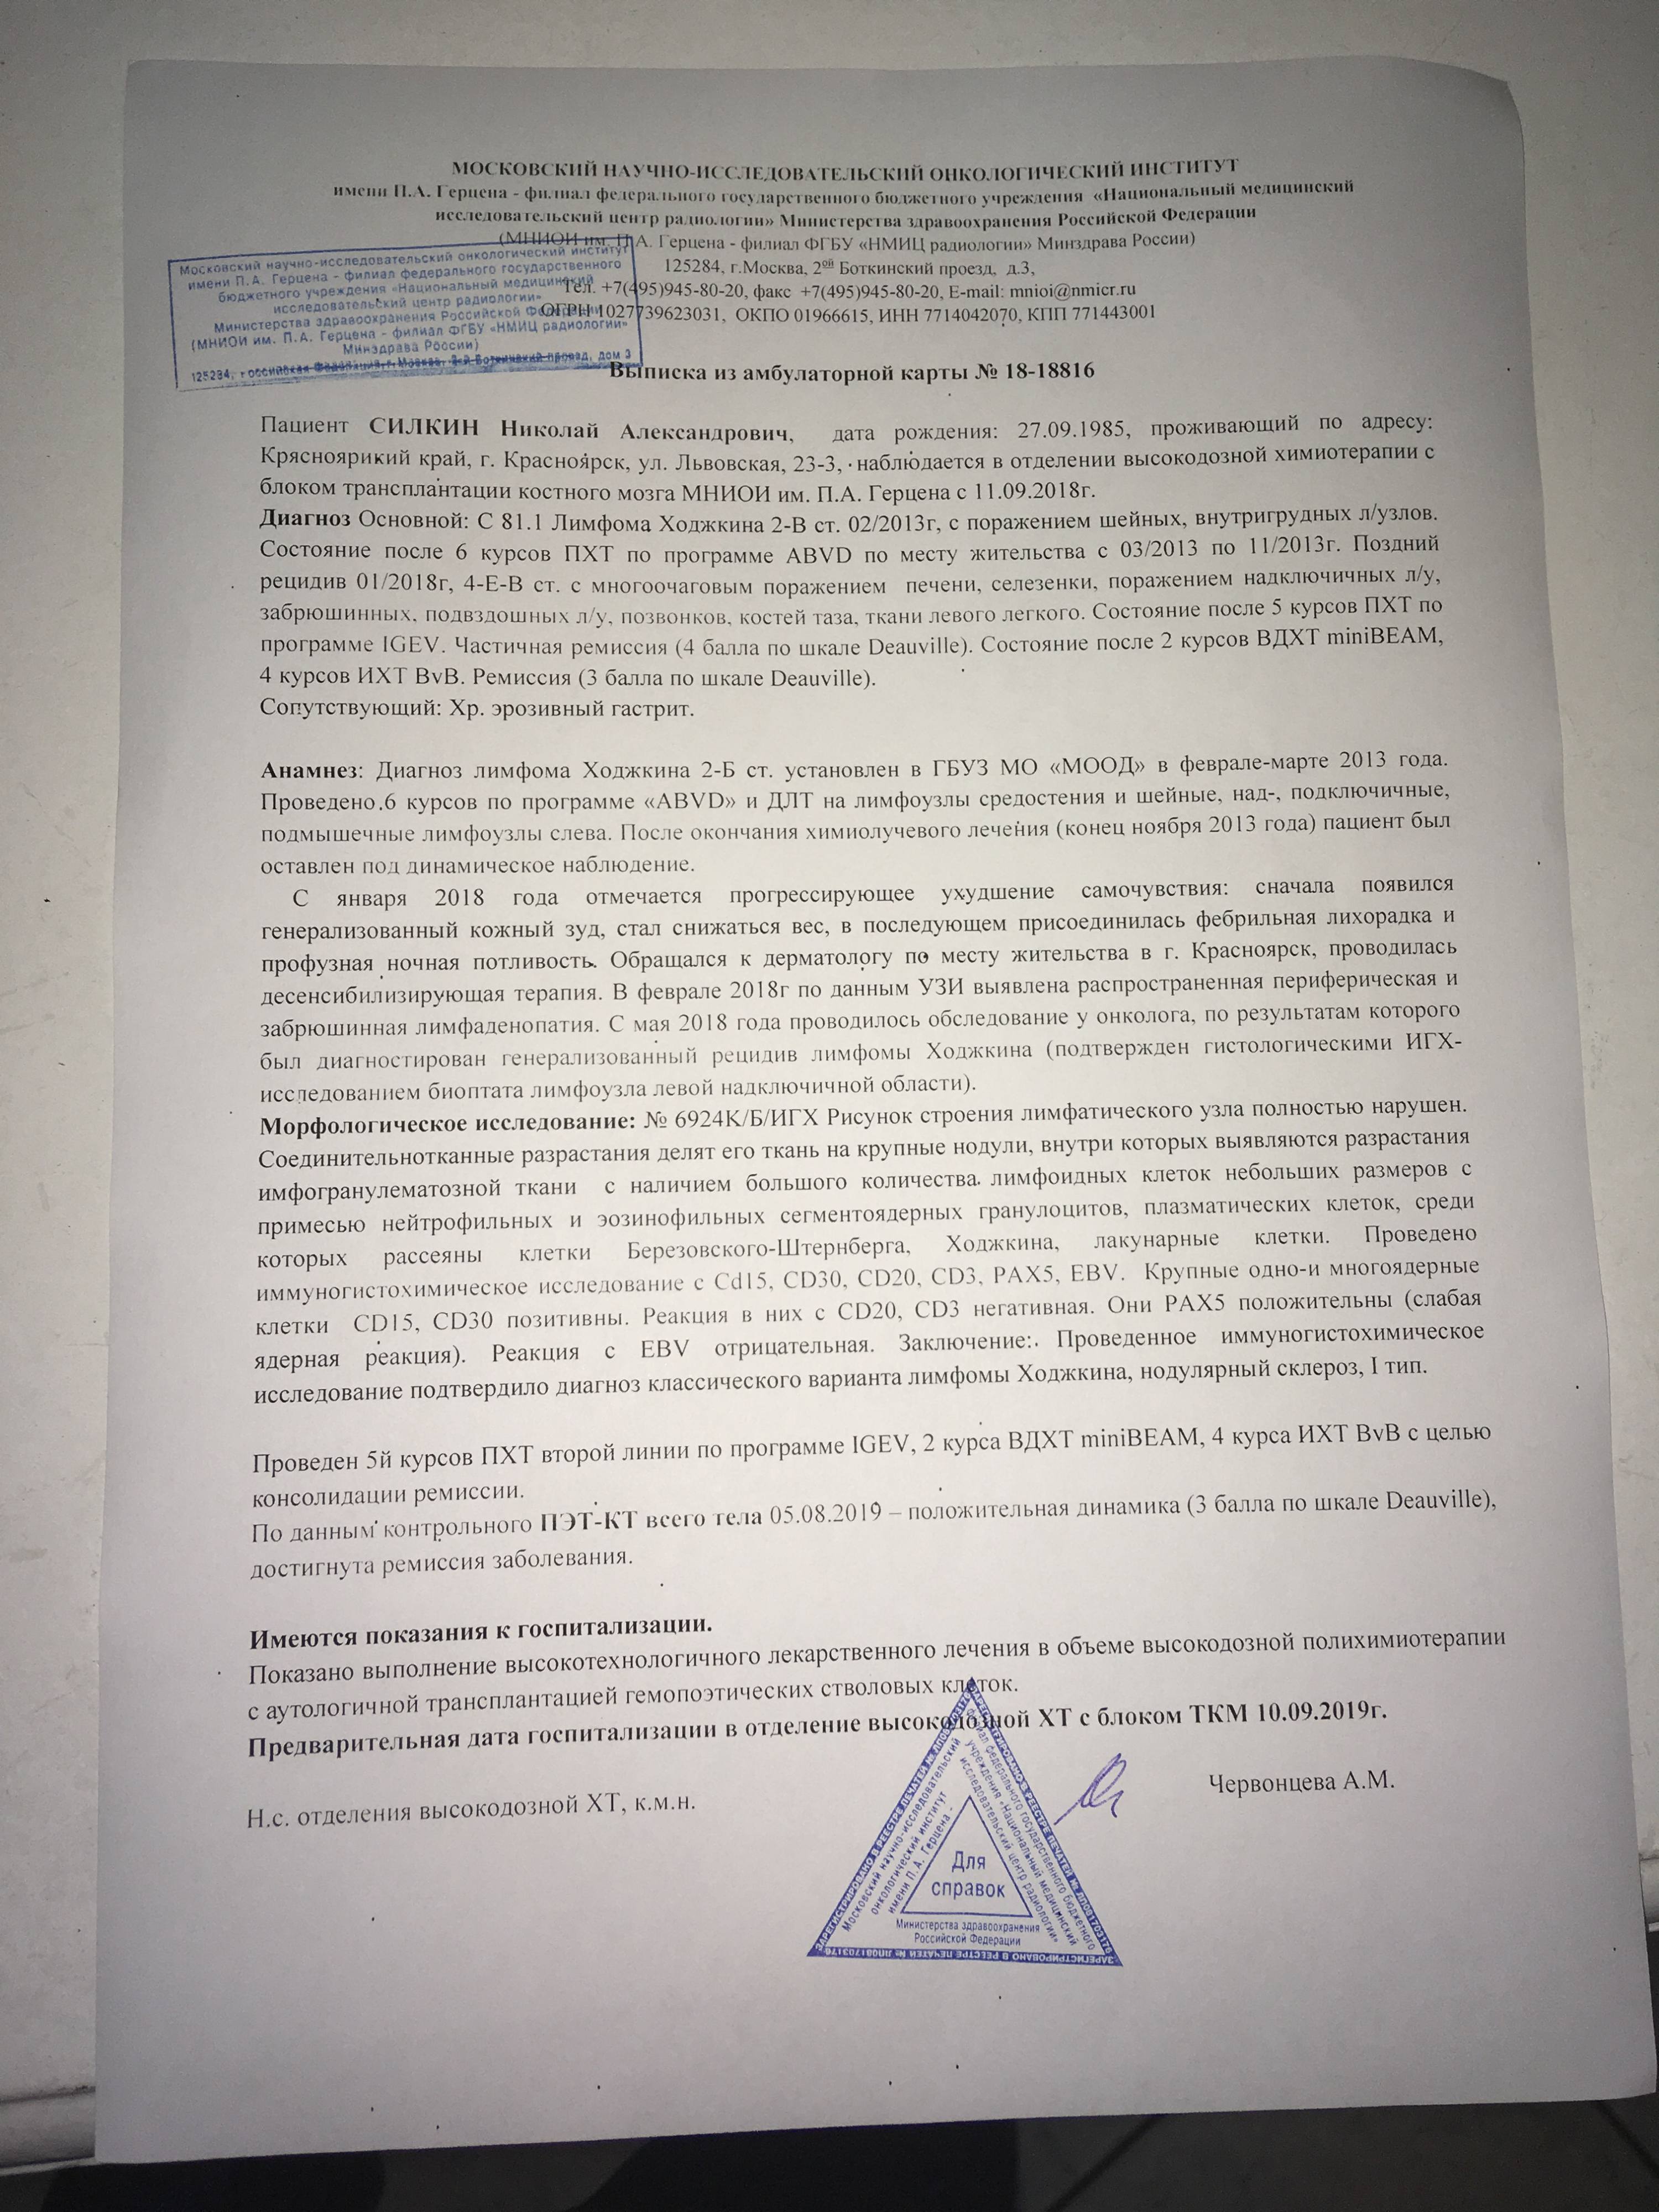

УЗИ лимфоузлов при лимфоме Ходжкина

Раздел: Образы вокруг